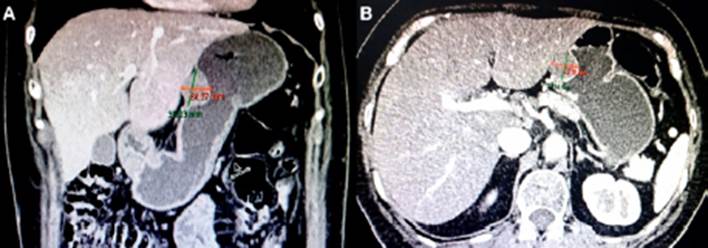

Presentamos el caso clínico de una paciente mujer de 57 años de edad quien consulta por epigastralgia y sensación de llenura precoz, en el examen endoscópico (Figura 1). Presentó doble lesión submucosa en cuerpo en cara anterior de 25 a 30 mm, y otra en antro, a nivel de curvatura mayor tercio medio de 15 x 18 mm. Ambas sospechosas de leiomiomas. Las imágenes de TAC abdominal muestran: dos formaciones expansivas localizadas a nivel de cuerpo, en la cara anterior y antro gástrico, que captan ligeramente contraste de 35,4 x 24 x 23,18 mm (Figura 2) y 24,94 x 20,13 x 18 mm (Figura 3), cuyas características son compatibles con: a. Leiomioma, b. Tumor de GIST.

Figura 2 A y B. Se aprecia lesión sólida expansiva de bordes bien definidos, con cierta captación a la sustancia de contraste localizada en el cuerpo hacia la cara anterior, de 35.03 mm de diámetro cráneo-caudal x 24 mm de diámetro ántero-posterior x 23.18 mm de diámetro transversal.